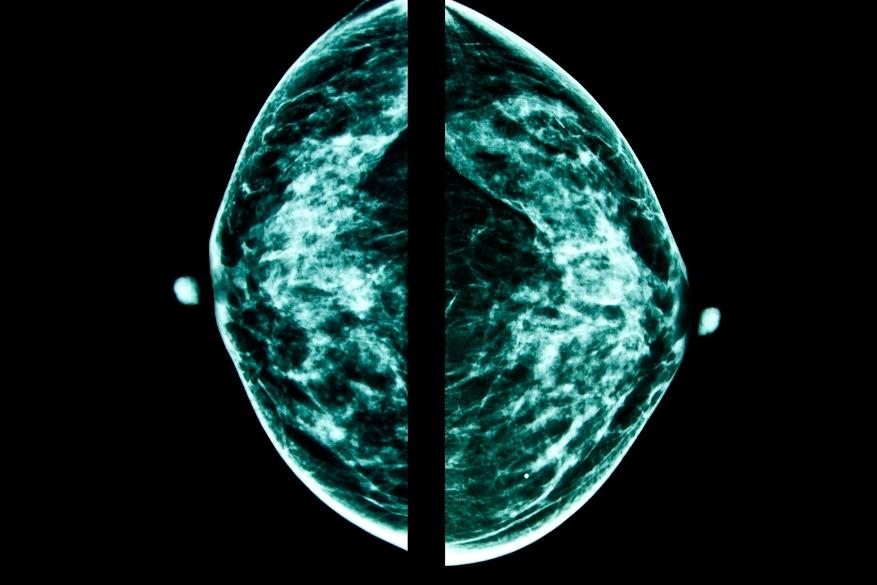

ΜΑΣΤΟΓΡΑΦΙΑ ΚΑΙ ΥΠΕΡΔΙΑΓΝΩΣΗ

Οι Αμερικανοί επιστήμονες παραδέχονται ότι η κυριότερη αρνητική πλευρά της μαστογραφίας είναι η υπερδιάγνωση, δηλαδή η διάγνωση καρκίνων που ποτέ δεν θα είχαν εξελιχθεί σε ιατρικό πρόβλημα στη διάρκεια ζωής μιας γυναίκας, είτε γιατί ο όγκος του μαστού ποτέ δεν θα μεγάλωνε, είτε γιατί θα μεγάλωνε τόσο αργά που τελικά η ασθενής θα πέθαινε από άλλη αιτία και όχι από καρκίνο του μαστού..

Ωστόσο με τις υπάρχουσες διαγνωστικές μεθόδους, είναι αδύνατον οι γιατροί να είναι σίγουροι ποιοι διαγνωσμένοι καρκίνοι θα αποδειχθούν ακίνδυνοι και ποιοι δυνητικά θανατηφόροι, συνεπώς αναγκάζονται -για προληπτικούς λόγους- να προχωρούν σε λιγότερο ή περισσότερο επιθετική αντικαρκινική θεραπεία.